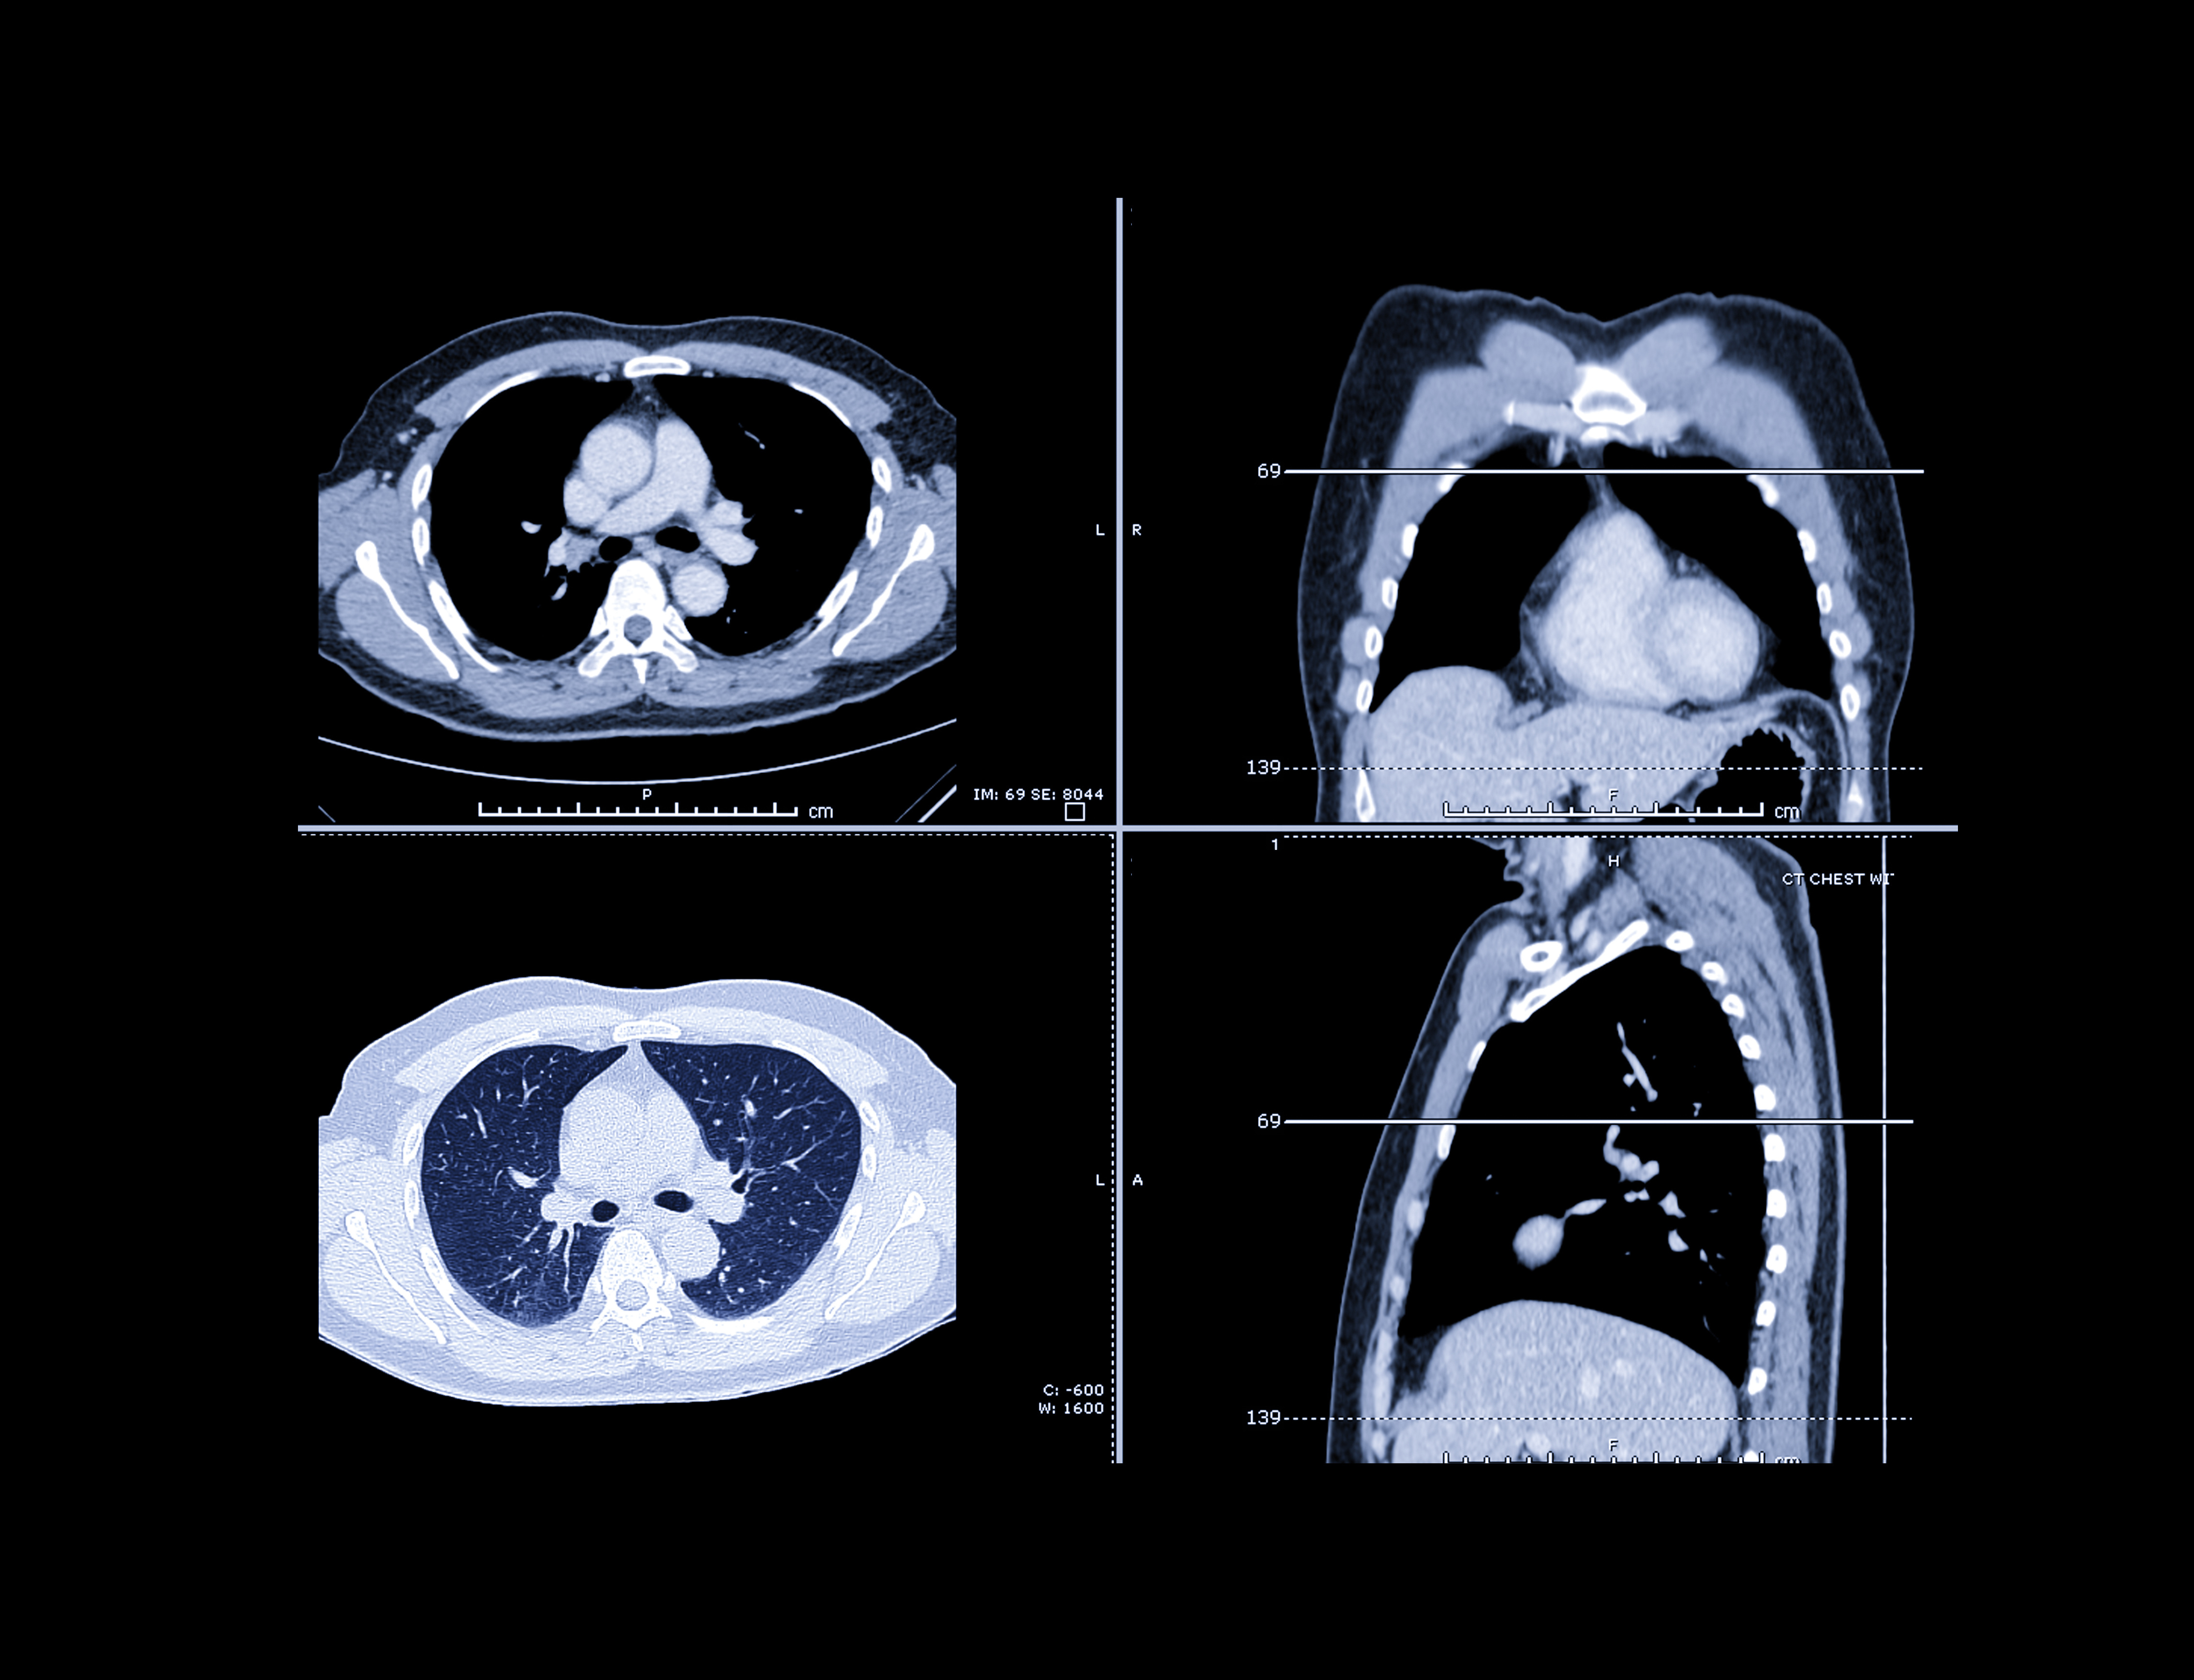

Advanced visualization and artificial intelligence (AI) software developer Coreline Soft has received clearance from the U.S. Food and Drug Administration (FDA) for its Aview LCS lung cancer screening computer-aided detection software.

Aview LCS helps clinicians identify and characterize lung nodules on low-dose CT (LDCT), cutting imaging interpretation time by 70%, increasing sensitivity by 34%, and decreasing false positives by 42%, according to Coreline Soft.